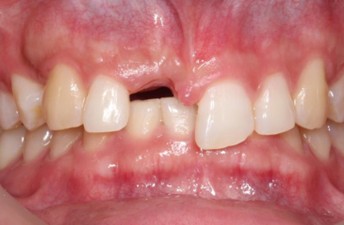

20代 男性

治療前

治療後

治療後- リスク・副作用

- 術後疼痛、歯肉腫脹

- 治療の費用

- 合計¥701,000(税込)

【内訳】

インプラント(1本)¥440,000

その他費用¥261,000

(薬・注射・レントゲン・CT・データ分析・骨造成・サージカルステント・血液検査・仮歯) - 年齢/性別

- 20代/男性

- 患者の具体的な症状

- 1年前に左上12 右上1の根の治療をし、その後放置していたら、左上2が破折した。

左上2インプラント補綴 左上1右上1オールセラミック装着。

歯根破折と虫歯による痛み、審美障害を主訴として来院。 - 検査方法

- コーンビームCT、レントゲン撮影

- 診断結果

- 左上2 歯根破折

- 治療詳細

- 左上抜歯後、インプラント埋入1本

骨造成あり 局所麻酔

インプラント治療後、左上1右上1セラミック修復2本 - 通院回数

- 9回

- 治療期間

- 12か月